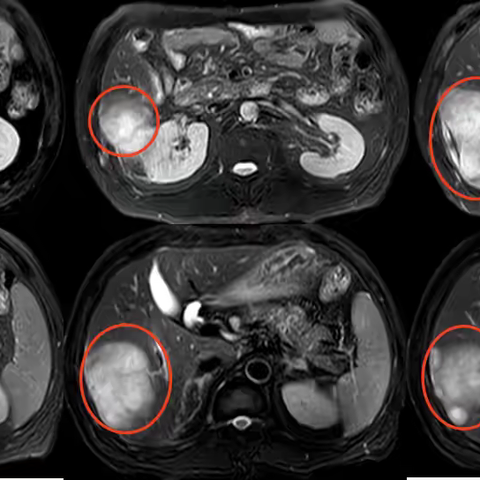

肾盂癌的放射性粒子植入治疗